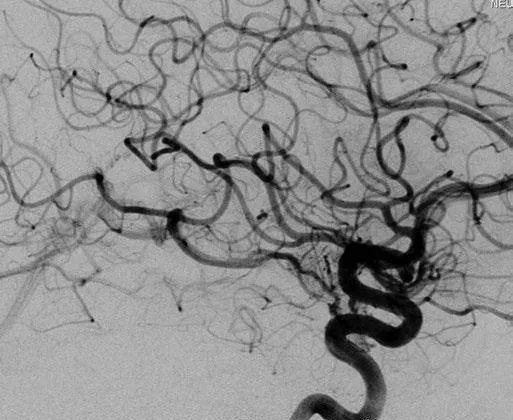

而就在伽马刀治疗3年后,造影显示AVM大部分闭塞,然而颞叶内侧少量残留畸形团向BVR引流(右ICA造影,侧位)。而现在想要解决颞叶内侧依然活跃的动静脉畸形,手术是Amanda的更优选择。

▼颞叶内侧少量残留畸形团向BVR引流(右ICA造影,侧位)